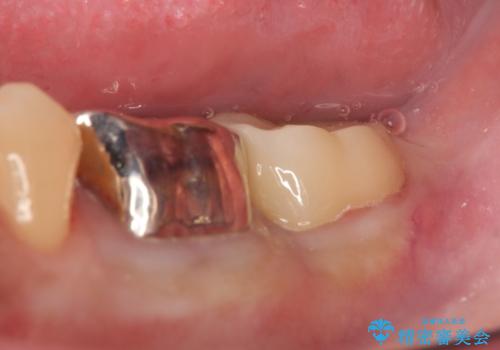

その後歯肉の回復を待ち、フルジルコニアクラウンにて補綴を行いました。

- フルジルコニアクラウン…¥70,000、歯冠長延長術…¥100,000費用は治療当時の料金となります